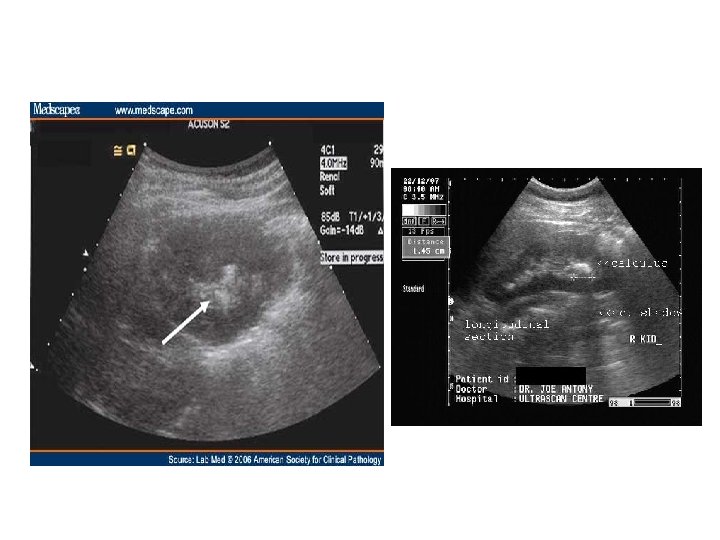

Radyolojik İnceleme • • • Direkt Üriner Sistem Grafisi Ultrasonografi İntravenöz Piyelografi Bilgisayarlı Tomografi Böbrek Sintigrafisi